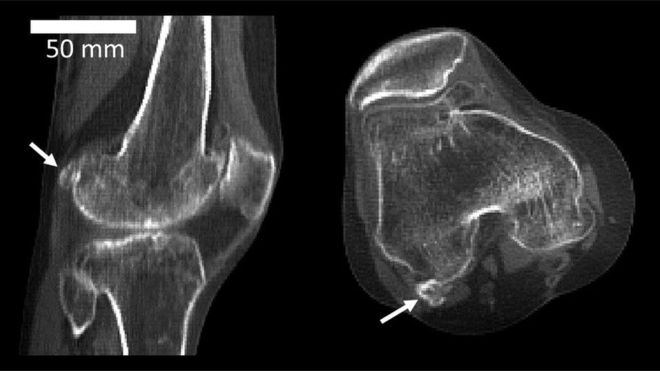

種子骨は「ファベラ fabella」とも呼ばれ、

これは「小さな豆」という意味のラテン語に由来します。

もっとも大きな種子骨は

膝関節の後ろ側にあります。